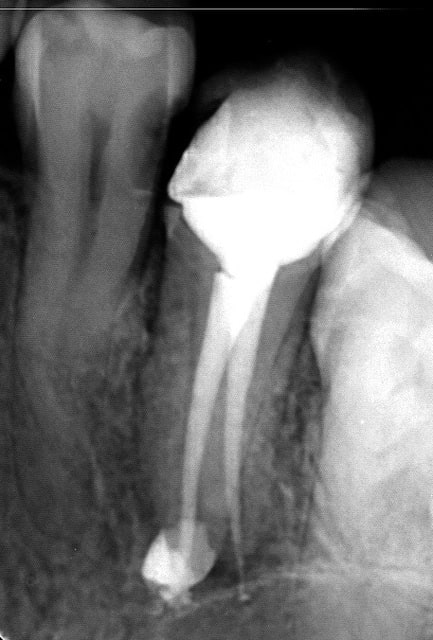

Je remets celles que j'ai faites hier on sait jamais si quelqu'un est intéressé (mais je venais sur ce post surtout pour avis dans la démarche.

Toutes mes endos d'hier (elles sont dans un autre sujet aussi)

Endo 1  1   preop f9tl26 - Eugenol

Endo 1  2  fin oyre3e - Eugenol

Endo 2 g96boc - Eugenol

Endo 8 l0w3t1 - Eugenol